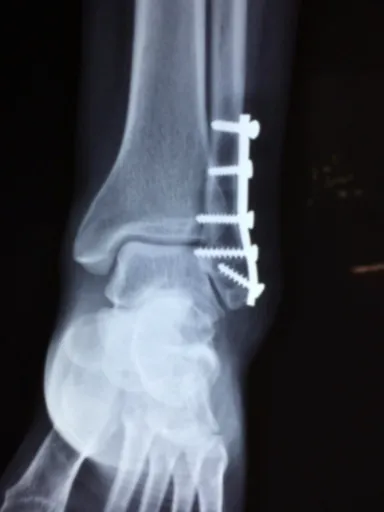

척추관 협착증을 정확하게 진단하기 위해서는 전문의의 진찰과 함께 다양한 검사가 필요합니다. 엑스레이 검사는 척추 뼈의 배열과 퇴행성 변화를 확인하는 데 도움이 되며, MRI 검사는 척추관의 좁아진 정도와 신경 압박 여부를 정확하게 파악할 수 있습니다. 또한, CT 검사는 뼈의 구조를 자세히 보여주어 척추관 협착증의 원인을 감별하는 데 유용합니다. 신경근전도 검사는 신경의 기능 이상을 평가하여 척추관 협착증으로 인한 신경 손상 정도를 파악하는 데 사용됩니다.

비수술적 치료로 증상이 호전되지 않거나, 다리 근력 약화, 마비, 대소변 기능 장애 등의 심각한 증상이 나타나는 경우에는 수술적 치료를 고려해야 합니다. 척추관 감압술은 좁아진 척추관을 넓혀 신경 압박을 해소하는 수술이며, 척추 유합술은 불안정한 척추 뼈를 고정하여 통증을 줄이는 수술입니다. 최근에는 최소 침습 수술 기법을 이용하여 흉터를 줄이고 회복 기간을 단축하는 수술법도 많이 시행되고 있습니다.